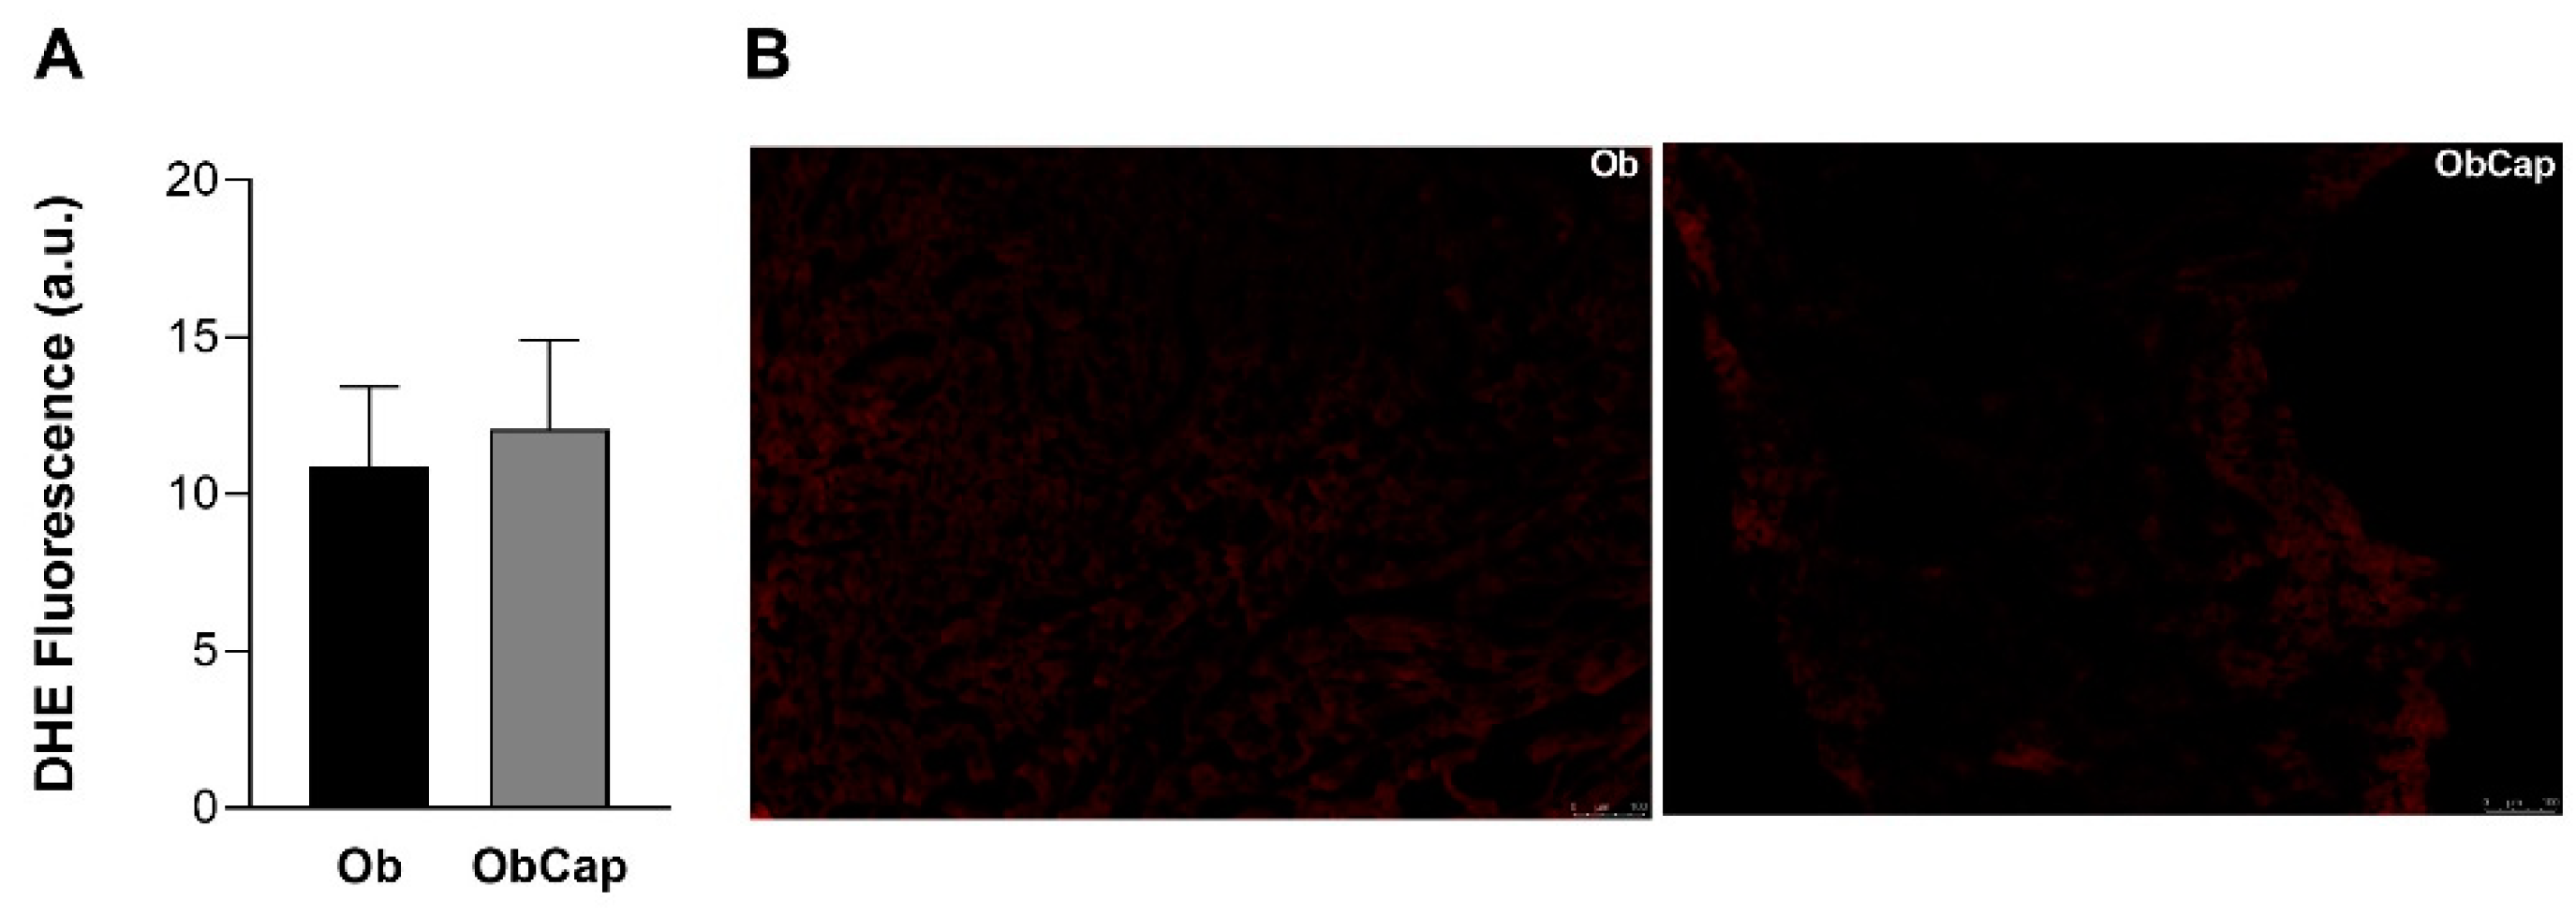

Furthermore, the production of superoxide radicals in situ in LV was verified using DHE as a marker. Obesity did not promote alterations in superoxide formation relative to the C group (C: 10.4 ± 2.8 a.u. vs. Ob: 10.9 ± 2.6 a.u.; C = Ob, p > 0.05). In addition, there was also no difference between the obese groups for this parameter (Figure 5).

Figure 5.

Analysis of superoxide formation in sections of cardiac tissue by the dihydroetidium fluorescence (DHE). (A) DHE Fluorescence. (B) Representative images of LV with DHE fluorescence. The scale bar is 100 μm. Groups Ob: obese (n = 6); ObCap: obese treated with capsinoids (n = 7). Values are expressed as mean ± standard deviation. Student t-test for independent samples.

In relation to oxidative biomarkers, in our study, no increase in superoxide levels by DHE was observed in obese animals, and no changes were observed due to treatment with capsinoids. This result may be due to the rapid conversion of superoxide to hydrogen peroxide inside the cells, which has a longer life cycle and permeates cell environments better, making it capable of causing persistent cellular changes, such as lipid and membrane oxidation and protein oxidation [61,63,64].